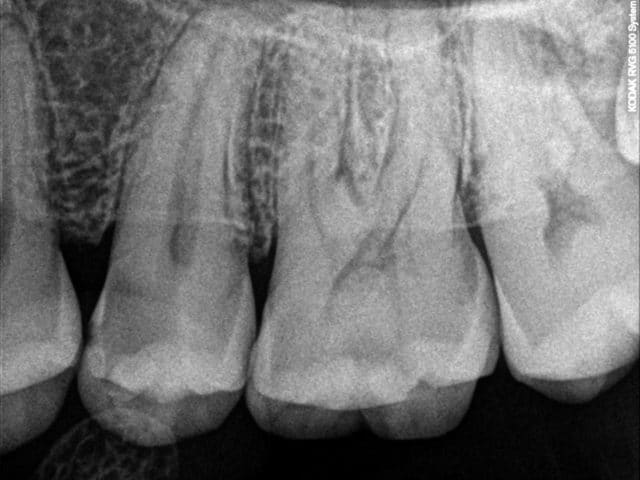

10/10/2015 à 19h51

Ce sont pas des soins particulierement immonde. Et si ca recidive, on peut se dire aussi que le patient doit avoir une hygiene degueu

Pas si degeux que ca. La patiente CMU qui à suivie elle avait un léger problème avec l'utilisation d'une brosse à dent et réellement un terrain polycarieux lié à l’hygiène.

Mais bon un petit becquet laissée par là à fait sont effet et a permis la multiplication des lésions carieuses.